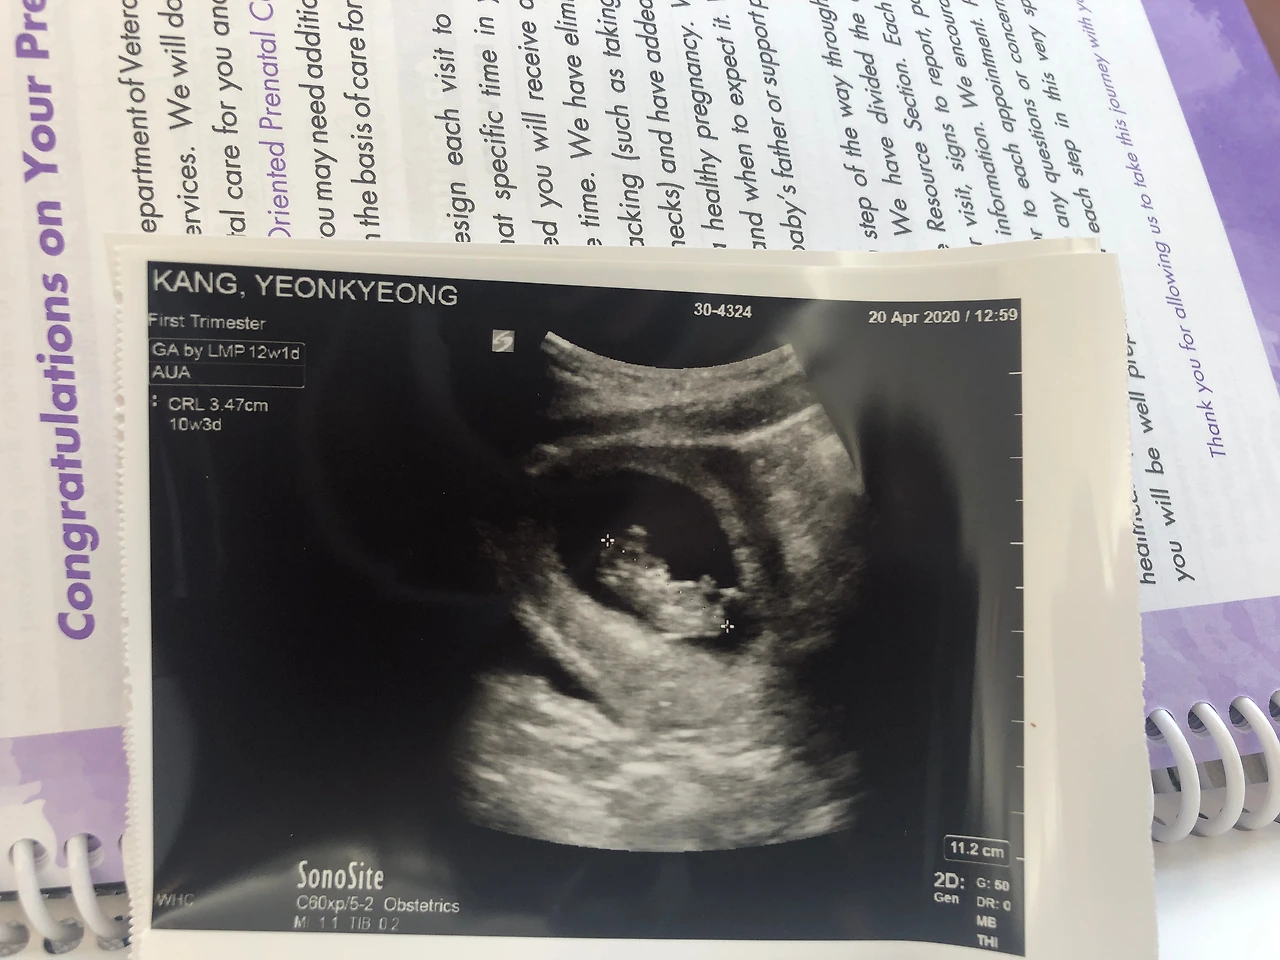

임신과 남편의 훈련과 코로나19가.

남편은 가장 강도가 높은 육군 훈련 중 하나라는 훈련에 들어가 임신 사실을 알게 된 후부터는 줄곧 나 혼자였다.

입덧이 가장 심할 시기인 임신 10-11주 차를 넘기고 있는 나로서는 이보다 더한 시련(?)은 없을 것 같았다.

임신 초기에 찾아오는 입덧은 생각보다 너무 힘들고(여기에서 힘들다는 건 그냥 힘든 게 아니라 울렁거림에 토, 소화불량에 변비 등등 게다가 얼마 전 입덧으로 응급실까지 다녀온 나였기에) 냄새에 한없이 예민해져선 음식을 만든다는 건 생각만으로도 너무 견디기 힘든 일이다.